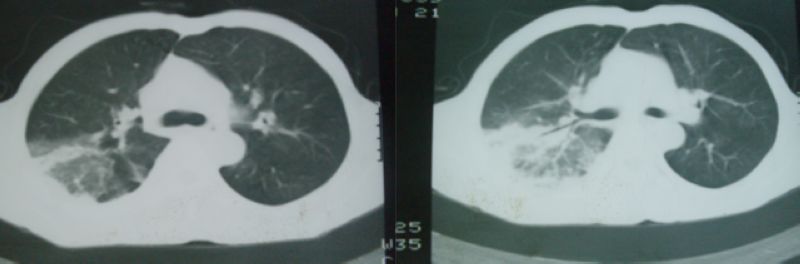

以下是引用hyhxn在2008-4-16 18:10:00的发言:[br]右中下肺炎症感染,没有纵隔窗?